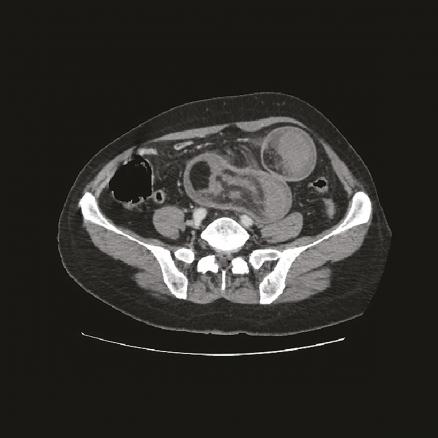

Cette femme de 62 ans était admise aux urgences pour des douleurs abdominales, des vomissements alimentaires et un arrêt des gaz, depuis 2 jours, sans fièvre. Elle avait pour antécédents une gastrite chronique, des douleurs abdominales intermittentes chroniques. L’examen notait une distension abdominale, une sensibilité abdominale diffuse ; les orifices herniaires étaient libres et l’ampoule rectale vide, sans melaena ni rectorragies. La pression artérielle était à 130/70 mmHg. L’échographie abdominale montrait une masse de la fosse iliaque gauche. La tomodensitométrie (TDM) abdominale révélait une masse ovalaire, hypodense, multistratifiée, avec un aspect en cocarde, ayant en son sein une incarcération mésentérique et en périphérie une lésion graisseuse en rapport avec un lipome (fig. 1 ). Le diagnostic d’invagination iléo-iléal secondaire à un lipome était évoqué. Une résection chirurgicale de 100 cm de grêle était réalisée (fig. 2 ).

L’invagination intestinale est définie par le télescopage et la pénétration d’un segment intestinal dans le segment d’aval. Elle survient essentiellement chez le nourrisson (80 % entre 6 mois et 2 ans).1 L’atteinte de l’adulte est rare. Selon les études précédentes, 1 et 5 % des invaginations intestinales aiguës s’observent chez l’adulte contre plus de 95 % chez l’enfant. Un lipome en est exceptionnellement la cause.2 Le diagnostic se fait par l’imagerie, plus rarement par la chirurgie. La TDM montre une masse tissulaire avec une alternance de zones concentriques en cocarde surmontée d’une image en croissant excentrée de densité graisseuse correspondant au boudin.1 Le traitement est chirurgical chez l’adulte, les causes organiques sous-jacentes étant les plus fréquentes.